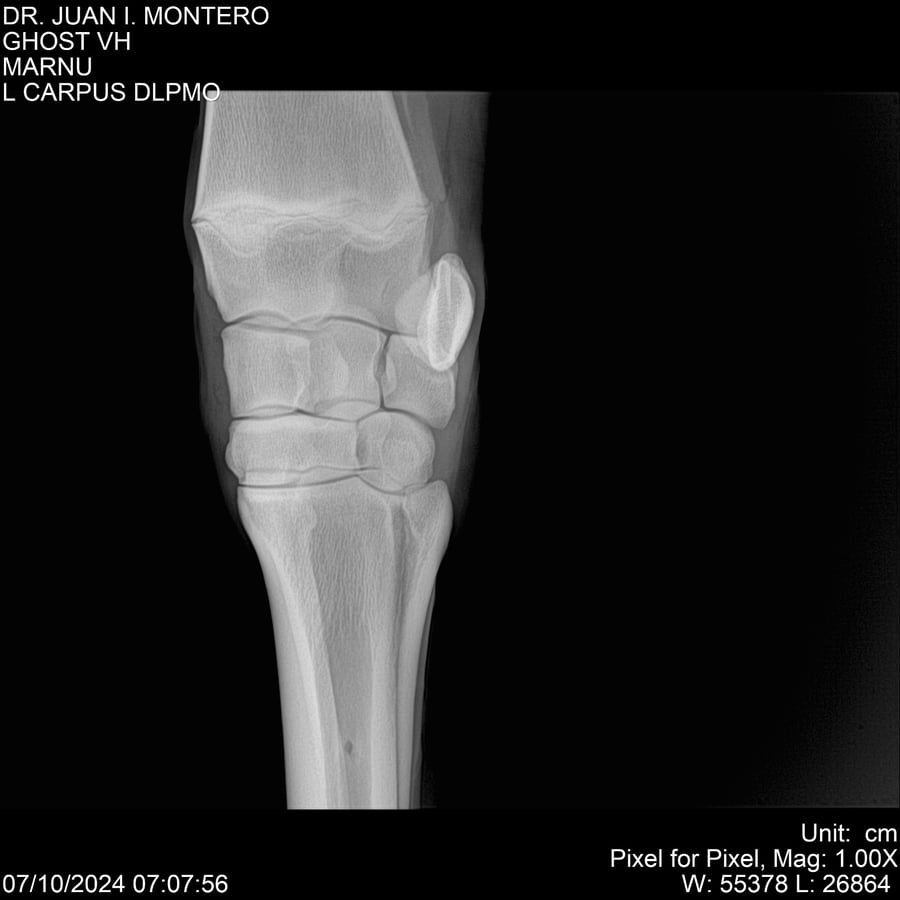

LOTE 15, GHOST VH 🔥 🔥 🔥 Lote Anterior Volver al remate Lote Siguiente Ficha Contacto Montevideo - Ficha del Lote Identificador: #282525 Categoría: Yeguarizos Montevideo - 69 Visualizaciones ClicData Contacto Empresa: Abelenda N. R., Walter Hugo Nombre*: Teléfono* : E-mail* : Mensaje Enviar Registrese gratis Este contenido Exclusivo está disponible sólo para usuarios registrados Ingresar